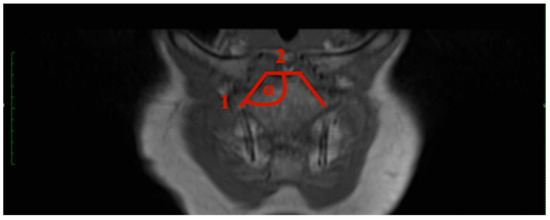

- Sternal angle: The sternal angle alpha was measured by the plug-in after the two tangents were drawn. Tangent 1 aligns at the sternal articular surface of the sternoclavicular joint, and tangent 2 is at the cranial end of the manubrium (Figure 1).